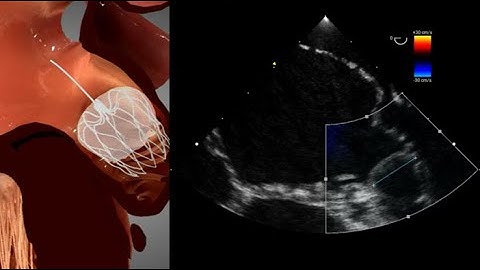

ECHO Guidance for Watchman Device- TEE Views for LAA sizing, Trans-septal Puncture and Implantation